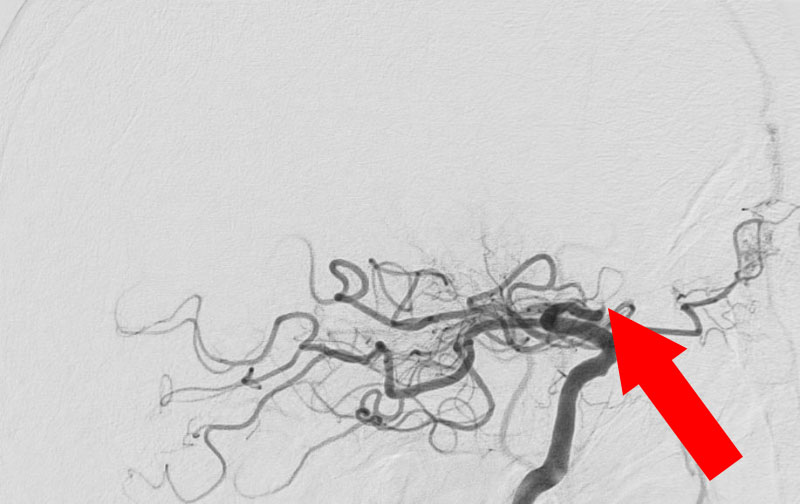

1317

'22年11月30日

心原性脳塞栓症

70代

救急外来

手術写真

治療

前

中

後

手術日